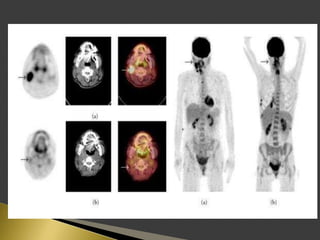

 PET using the radio-labeled glucose analog 18F-FDG has great

importance in lymph node imaging.

 PET supplies a semi-quantitative metabolic characterization of

tissues that may help to predict tumor behavior.

 The sensitivity and specificity of 18F-FDG PET for identification

of lymph node metastases on a neck level-by-level basis were

higher than those of CT/MRI.

 The incorporation of functional information derived from PET

has the potential factor to improve prognostic stratification and

treatment planning for patients.

 Patients were instructed to fast for 6 h before the PET study.

 18F-FDG was administered intravenously.

 For PET/CT scans, oral contrast was administered to patients

during the uptake time.

 No IV contrast material was administered for CT scans.

 Head to mid thigh scans were obtained for all patients.

 PET and CT images were acquired 50 min after the injection of

18F-FDG.

 PET, CT, and fused PET/CT images were available for review

and were displayed in axial, coronal, and sagittal planes.

 PET data were displayed as non-corrected and attenuation-

corrected images as well as in a rotating MIP.

 Area of increased 18F-FDG uptake with intensity higher than

that of surrounding tissues and did not correspond to the

physiologic bio-distribution of the radiotracer, were defined as

positive.

 18F-FDG activity only in areas of the physiologic tracer bio-

distribution or no sites of increased uptake were considered

negative.

 The highest activity within a region of interest was measured.

 The standardized uptake value (SUV) was determined as the

highest activity concentration per injected dose per body weight

(kg).

 18F-FDG uptake was graded visually on the following 5-point

scale:

 0-definitely benign, no uptake.

 1-probably benign, 2.3 (range, 1.4–4.0).

 2-equivocal, 2.6 (range, 1.4–4.4).

 3-probablymalignant, 3.5 (range, 2.1–7.9).

 4-definitely malignant, 6.6 (range, 2.6–24.5).

 SUV of 3.1 was used as the cutoff for positive PET results.